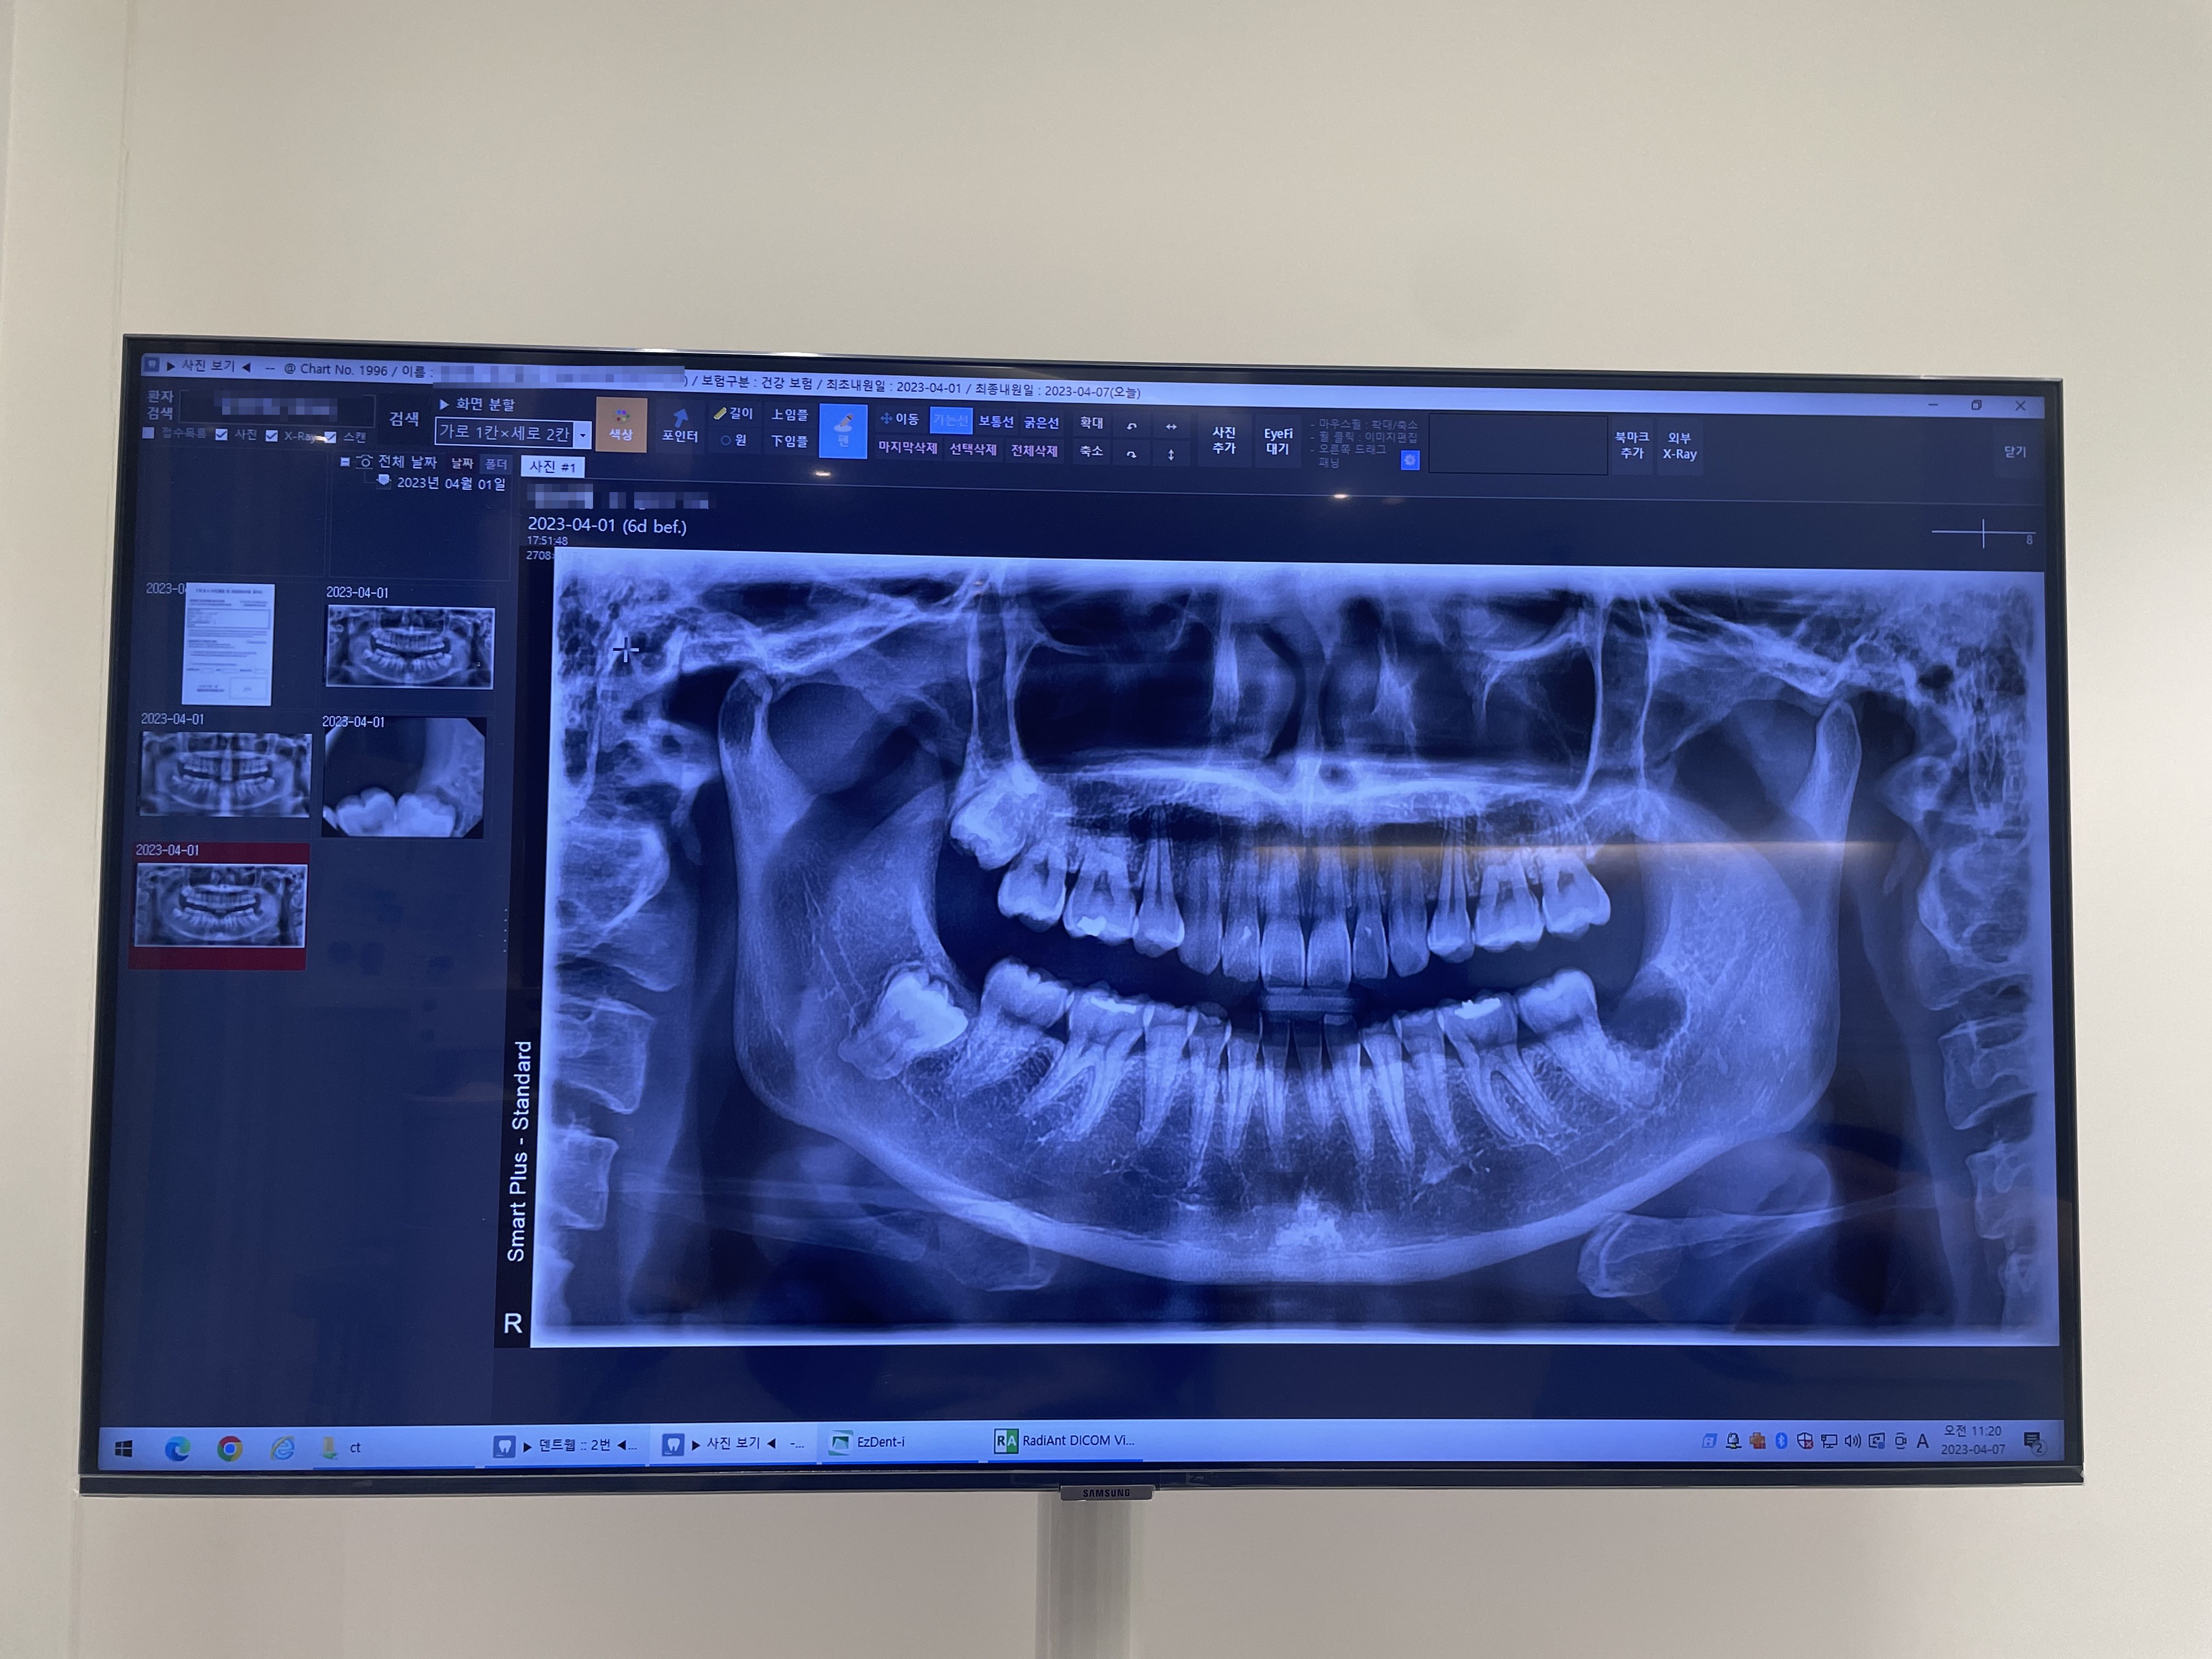

진료 의자 앞에는 크은 모니터가 있고 발치한 후의 엑스레이도 보여줍니다.